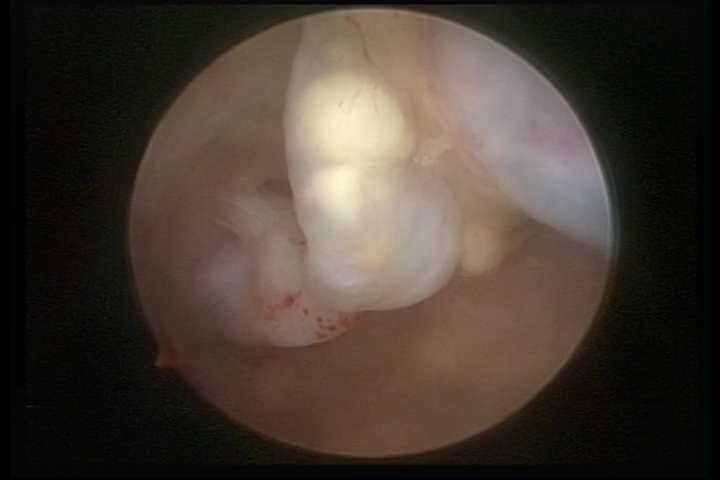

It may present a variable range of macroscopic aspects, with a pseudolopypoid aspect; resembling cerebroid tissue or presenting a decidual reaction; superficial vascularization is more evident presenting vessels in the shape of corkscrew or spirals also viewing the vascularization with atypias, with an increase on the thickness of the superficial vessels, tissue in necrosis and small dendrites (papillomatous) may be found.